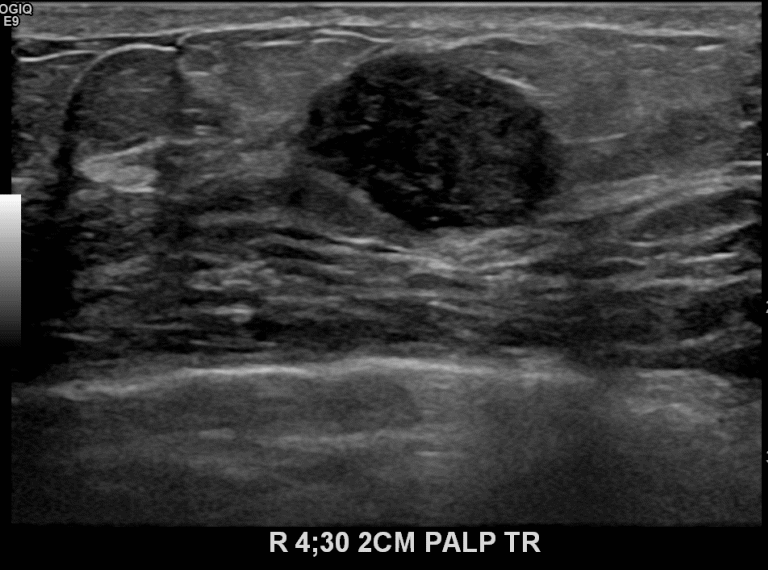

상기환자 4개월전부터 우측유방에 멍울잡혀 내원하신 분으로 초음파시행 후

우측4시방향에 악성의심되어 조직검사 후 유방암진단되었습니다.